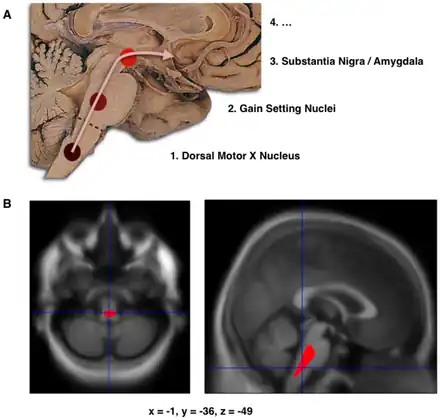

a)Schematic initial progression of Lewy body deposits in the first stages of Parkinson's disease, as proposed by Braak and colleagues, b)Localization of the area of significant brain volume reduction in initial PD compared with a group of participants without the disease in a neuroimaging study, which concluded that brainstem damage may be the first identifiable stage of PD neuropathology[68]